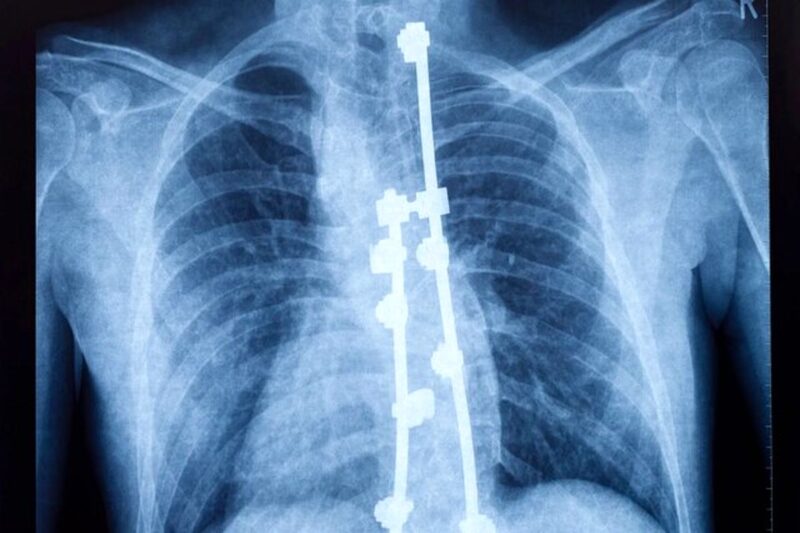

محققان دانشگاه کالیفرنیا در ریورساید از یک نوآوری رونمایی کردهاند که امکان تصویربرداری با وضوح بالا از نخاع انسان در حین جراحی را فراهم میکند. آنها آن را «تصویربرداری سونوگرافی کاربردی» (fUSI) مینامند.

این فناوری برای پزشکان دیدی از نخاع فراهم میکند و همچنین نقشهبرداری در لحظه از پاسخ طناب نخاعی به درمانهای مختلف را ممکن میکند. این فناوری میتواند کاربردهای بی حد و حصری داشته باشد، بهویژه برای کاهش درد میلیونها نفر در سراسر جهان که از کمردرد مزمن رنج میبرند.

واسیلیوس کریستوپولوس (Vasileios Christopoulos)، استادیار مهندسی زیستی در دانشگاه کالیفرنیا ریورساید، پیشگام استفاده از «تصویربرداری سونوگرافی کاربردی» برای تصویربرداری از نخاع بود. برخلاف روشهای سنتی مانند تصویربرداری رزونانس مغناطیسی عملکردی (fMRI)، «تصویربرداری سونوگرافی کاربردی» دارای تحرک قابلتوجهی است. این سیستم نیاز به زیرساختهای گسترده ندارد و ابزاری همه کاره برای محیطهای مختلف پزشکی است.

گروه تحقیقاتی برای نمایش «تصویربرداری سونوگرافی کاربردی» با مرکز بازسازی عصبی USC در بیمارستان کک (Keck) همکاری کردند. کریستوپولوس این فناوری را روی ۶ بیمار آزمایش کرد.

این بیماران که از درمانهای دیگر تسکینی پیدا نکردند، تحت تحریک نخاع با الکترود قرار گرفتند. هدف کاهش ناراحتی آنها و افزایش کیفیت کلی زندگی آنها بود.

فعالسازی با تحریک نخاعی

کریستوپولوس با توضیح نکته منطقی که پشت تحریک طناب نخاعی وجود دارد، گفت: اگر دستت را به جایی بکوبی، به طور غریزی، آن را مالش میدهی. مالش جریان خون را افزایش میدهد، اعصاب حسی را تحریک میکند و سیگنالی به مغز میفرستد که درد را پنهان میکند. ما معتقدیم که تحریک طناب نخاعی ممکن است به همین صورت عمل کند، اما ما به راهی برای مشاهده فعال شدن نخاع در نتیجه تحریک نیاز داشتیم.

این موفقیت به کاهش چالشهای قبلی کمک میکند که در آنها ارزیابی اثربخشی چنین درمانهایی به دلیل اختلال در بیهوشی و ناتوانی در ارائه بازخورد شفاهی توسط بیماران مشکل بود.

با این فناوری ما میتوانیم تغییرات جریان خون در نخاع که ناشی از تحریک الکتریکی است را کنترل کنیم. کریستوپولوس ادامه داد: این میتواند نشانهای از کارآمد بودن درمان باشد. این توانایی برای مشاهده پاسخهای فیزیولوژیکی در لحظه در طول جراحی، متحول کننده خواهد بود و نوید درک بهتری از اثربخشی مداخلات برای کمردرد مزمن را ارائه میدهد.

محققان در مورد این نوآوری هیجان زدهاند، زیرا روشهای تصویربرداری سنتی برای نفوذ به پیچیدگیهای نخاع با سختی مواجه هستند. آنها به دلیل حرکات مصنوعی ناشی از تپش قلب و تنفس با مشکل مواجه بودند.

با این حال، رویکرد منحصر به فرد «تصویربرداری سونوگرافی کاربردی» حساسیت به چنین مصنوعاتی را به حداقل میرساند. این دستگاه مانند سونار زیردریایی که از امواج صوتی برای حرکت و شناسایی اشیاء زیر آب استفاده میکند، کار میکند. امواج صوتی منتشر شده در ناحیه مورد نظر تصاویر واضحی را بر اساس پژواک تولید شده توسط گلبولهای قرمز ایجاد میکنند.

تحقیقات این گروه از محققان توانایی «تصویربرداری سونوگرافی کاربردی» را در تشخیص تغییرات جریان خون در سطوح کمتر از یک میلیمتر در ثانیه نمایان میکند.

سطح دقت آن از روشهای سنتی مانند افامآرای که فقط میتواند تغییرات دو سانتیمتری در ثانیه را تشخیص دهد، پیشی میگیرد.